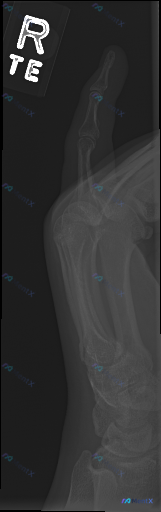

整理了一张右侧手部侧位X光片的影像资料,先把客观的影像表现放出来,大家第一眼会怎么判断? 客观影像表现(已整理) 1. 骨骼与关节:右侧第一掌骨基底部可见明显皮质中断、骨折线,有骨块分离,关节面紊乱;第一腕掌关节(CMC关节)对位严重失常,掌骨基底部向背侧/桡侧移位,关节间隙消失。 2. 其他关节:...